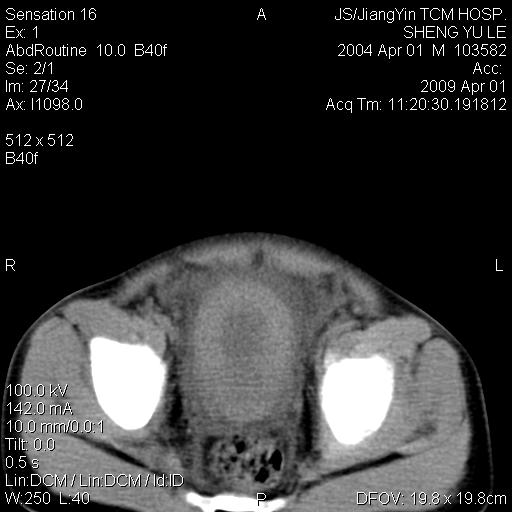

m,5岁。尿痛尿频数天。既往无病史。ct平扫腹盆腔积液。膀胱壁明显增厚。另可见心包增厚。wbc5万,骨髓穿等结果。请指教。

膀胱影像表现结合临床应该是急性膀胱炎症,但为什么有腹水呢?双肾输尿管无扩张,泌尿系压力应该不大不至于引起尿外渗,应该是腹膜感染引起的,但楼主没有提及相关症状,腹膜及膀胱结核?患者白细胞5万(结核不至于这么高啊),脾脏增大,是不是有白血病?进一步检查。。